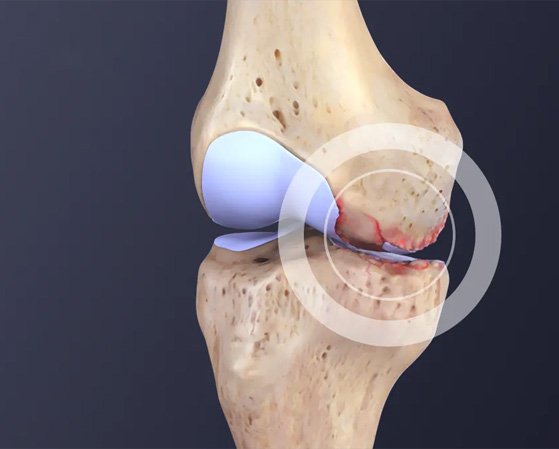

Repair of Damaged Cartilage

In early knee arthritis, the protective cartilage that covers the joint surface begins to wear away, leading to pain and inflammation. PRP treatment provides a unique advantage in promoting cartilage repair by stimulating the production of collagen and proteoglycans, the essential components of healthy cartilage. Clinical studies have shown that PRP can enhance the regeneration of cartilage, slowing down the progression of knee arthritis and improving joint function.